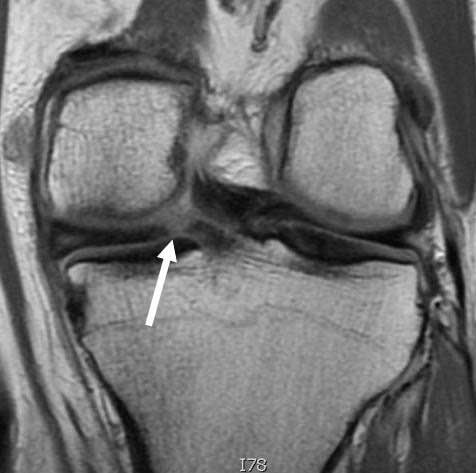

قطع غضروف الركبة من الدرجة الثالثة هو أشد درجات تمزق الغضروف الهلالي، حيث يكون هناك تمزق كامل يصل إلى سطح الغضروف، ويؤدي إلى انفصال جزء منه أو تحركه داخل المفصل.

- يكون التمزق واضحًا في أشعة الرنين المغناطيسي.

- الدرجة الثالثة

تمزق كامل يصل لسطح الغضروف، وهو ما يُعرف بـ تمزق غضروف الركبة الكامل، وغالبًا يحتاج لتدخل علاجي مكثف.